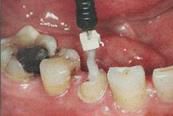

在操作的過程中要注意無菌操作,保證纖維樁的無菌狀態(tài)。推薦將樹脂核堆好之后再截斷纖維樁,而不是截斷后再粘接。如下圖: